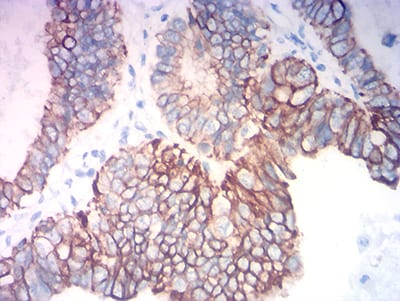

分类: 科研抗体货号: 31757别名: K18; CK-18; CYK18应用: WB,IHC,IF,FCM反应种属: Human

分类: 科研抗体货号: 31772别名: K18; CK-18; CYK18应用: WB,IHC,IF,FCM反应种属: Human